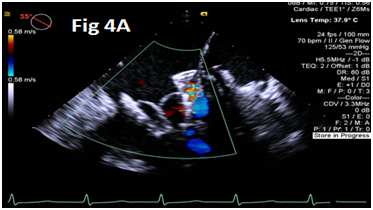

A 73-year-old female with mechanical mitral valve, tricuspid annuloplasty (32mm Edwards Physio Tricuspid incomplete ring) underwent Transcatheter Tricuspid Valve Replacement (TTVR) using off-label 29mm Edwards Sapien 3 (S3) Transcatheter Heart Valve (THV). Immediate post valve deployment, mild Perivalvular Leak (PVL) was noticed at the septal aspect (area of incomplete annuloplasty ring). Eighteen months later, patient presented with recurrent right heart failure and paracentesis due to severe tricuspid PVL (Figure 1A-C, Video 1). Percutaneous PVL closure under general anesthesia, Trans-esophageal Echocardiography (TEE) was performed. Via femoral venous access, defect was easily crossed with Agilis steerable sheath, multipurpose catheter and 0.035” glide wire. Despite recurrent attempts, wire came through the PVL but then traversed through open cells of S3 into the right ventricle (Figure 2A), confirmed with Armada 6mm balloon waist at the S3 cage (Figure 2B) (despite inflating 28mm Z med balloon inside S3 cage, Figure 2C). We decided to partially deploy the plug and assess valve function. Using 7.5F Asahi Eaucath multipurpose guide, a 12mm AmplatzerTM Vascular plug II (AVP II) was advanced through the defect. The ventricular disc was opened inside the S3 cage while body in the PVL defect (outside the S3 cage) and atrial disc on the atrial side of PVL (Figure 3A-B). With S3 function unaffected, no central leak and minimal gradient, PVL reduced to mild severity (Figure 4A-D, Video 2); the AVP II was successfully deployed (Figure 5). At 3-month follow up, there was an excellent symptomatic improvement (NYHA functional class I), with no heart failure re-hospitalization or paracentesis. Deployment of plug disc inside the valve frame is not recommended due to fear of interference with leaflet function and possible injury in long term. There was no immediate issue with the valve function in this case (due to space between the leaflet and frame of S3 and depends on size of plug used). Valve-in-Valve (S3-in-S3) would have certainly sealed all open cells treating this PVL but is more expensive option.

Figure 4 Post AmplatzerTM vascular plug II with mild residual PVL (4A), mildly elevated trans-S3 gradient (4B) and normal leaflet mobility of S3 (diastole 4C, Systole 4D).